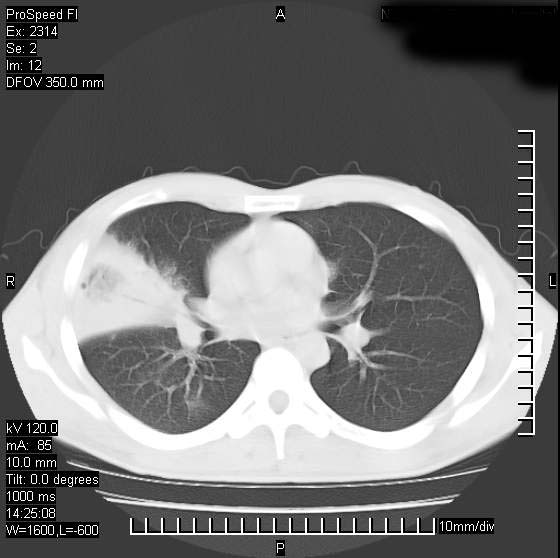

男性,再生障碍性贫血,入院前发热10天,最高40c,右侧胸痛,外院ct示右上,中肺边缘模糊的球性影(就是我现在图中标示的范围),考虑炎症,在我院使用头孢呋辛,洛美沙星10天,高烧消退,自感下午稍有发热,但今天ct示右上,中肺病灶明显扩大,还是考虑炎症,看其中的球型影是否霉菌感染??,是否能排除结核?

右肺中叶外侧段病变,上缘界限不清,下缘锐利,以段性发病为主,内见巨大空洞及空洞内容物,结合病史首先考虑:化脓性肺炎。不除外霉菌感染!

片状高密度影内见空洞影,内可见球形软组织密度影,并有新月征,考虑霉菌感染.

支持右肺上叶、中叶外侧段节段性肺炎伴脓肿形成。